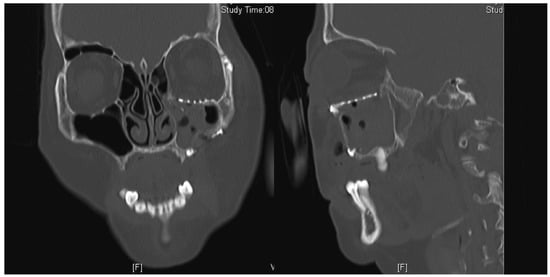

A 40-year-old man underwent an open reduction internal fixation (ORIF) of his right zygomaticomaxillary complex (ZMC) fracture and orbital floor reconstruction for a right orbital floor fracture, sustained after a road traffic accident (Figure 1). He had no preoperative diplopia.

The surgery took place 10 days following the accident due to neurosurgical concerns regarding his brain injury. Intraoperatively, the periorbita surrounding the herniated contents was noted to be disrupted. A 0.4-mm titanium curved plate was used to reconstruct the orbital rim, and the medium 0.4-mm precontoured titanium orbital plate (Figure 2) was used for reconstruction of the orbital floor defect (DePuy Synthes, Johnson & Johnson, Solothurn, Switzerland). Intraoperatively, he had a negative forced-duction test and postoperatively, he was noted to have full range of extraocular movements of his right eye. The postoperative CT scan demonstrated anatomical placement of the orbital floor plate with reduction of all periorbita (Figure 3).

Figure 1. Coronal and sagittal cuts of the CT scan of the face (Case 1) demonstrating the presence of a large right orbital floor defect (arrows).